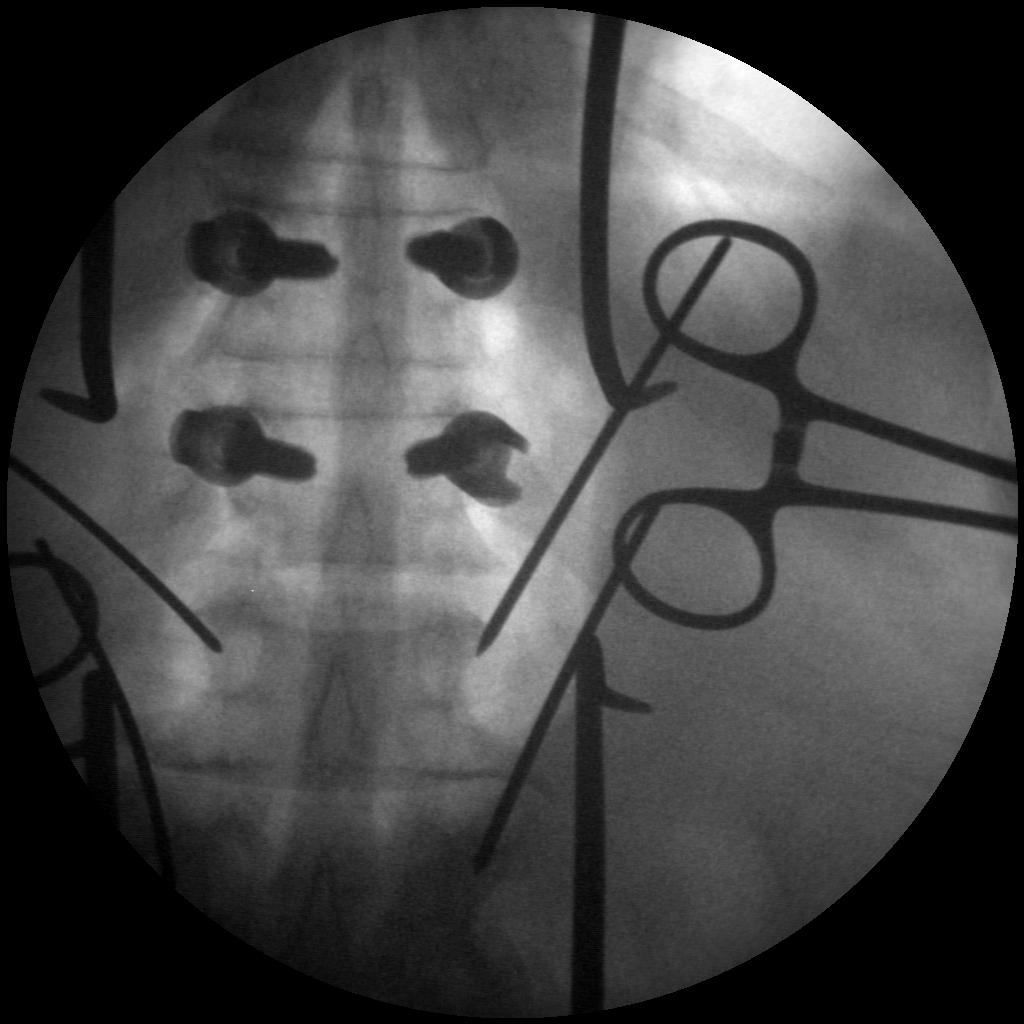

Skan-C uses advanced imaging technology, such as pulsed fluoroscopy and digital subtraction angiography, to provide highly detailed images of the affected area. This allows doctors to perform procedures with increased precision and accuracy, and better patient outcome

Skan-C provides 45 degree over rotation (over scan) that is particularly helpful for pain management applications. Skan-C is designed to be user-friendly, with an intuitive interface that allows doctors to quickly and easily adjust settings and customize imaging parameters.